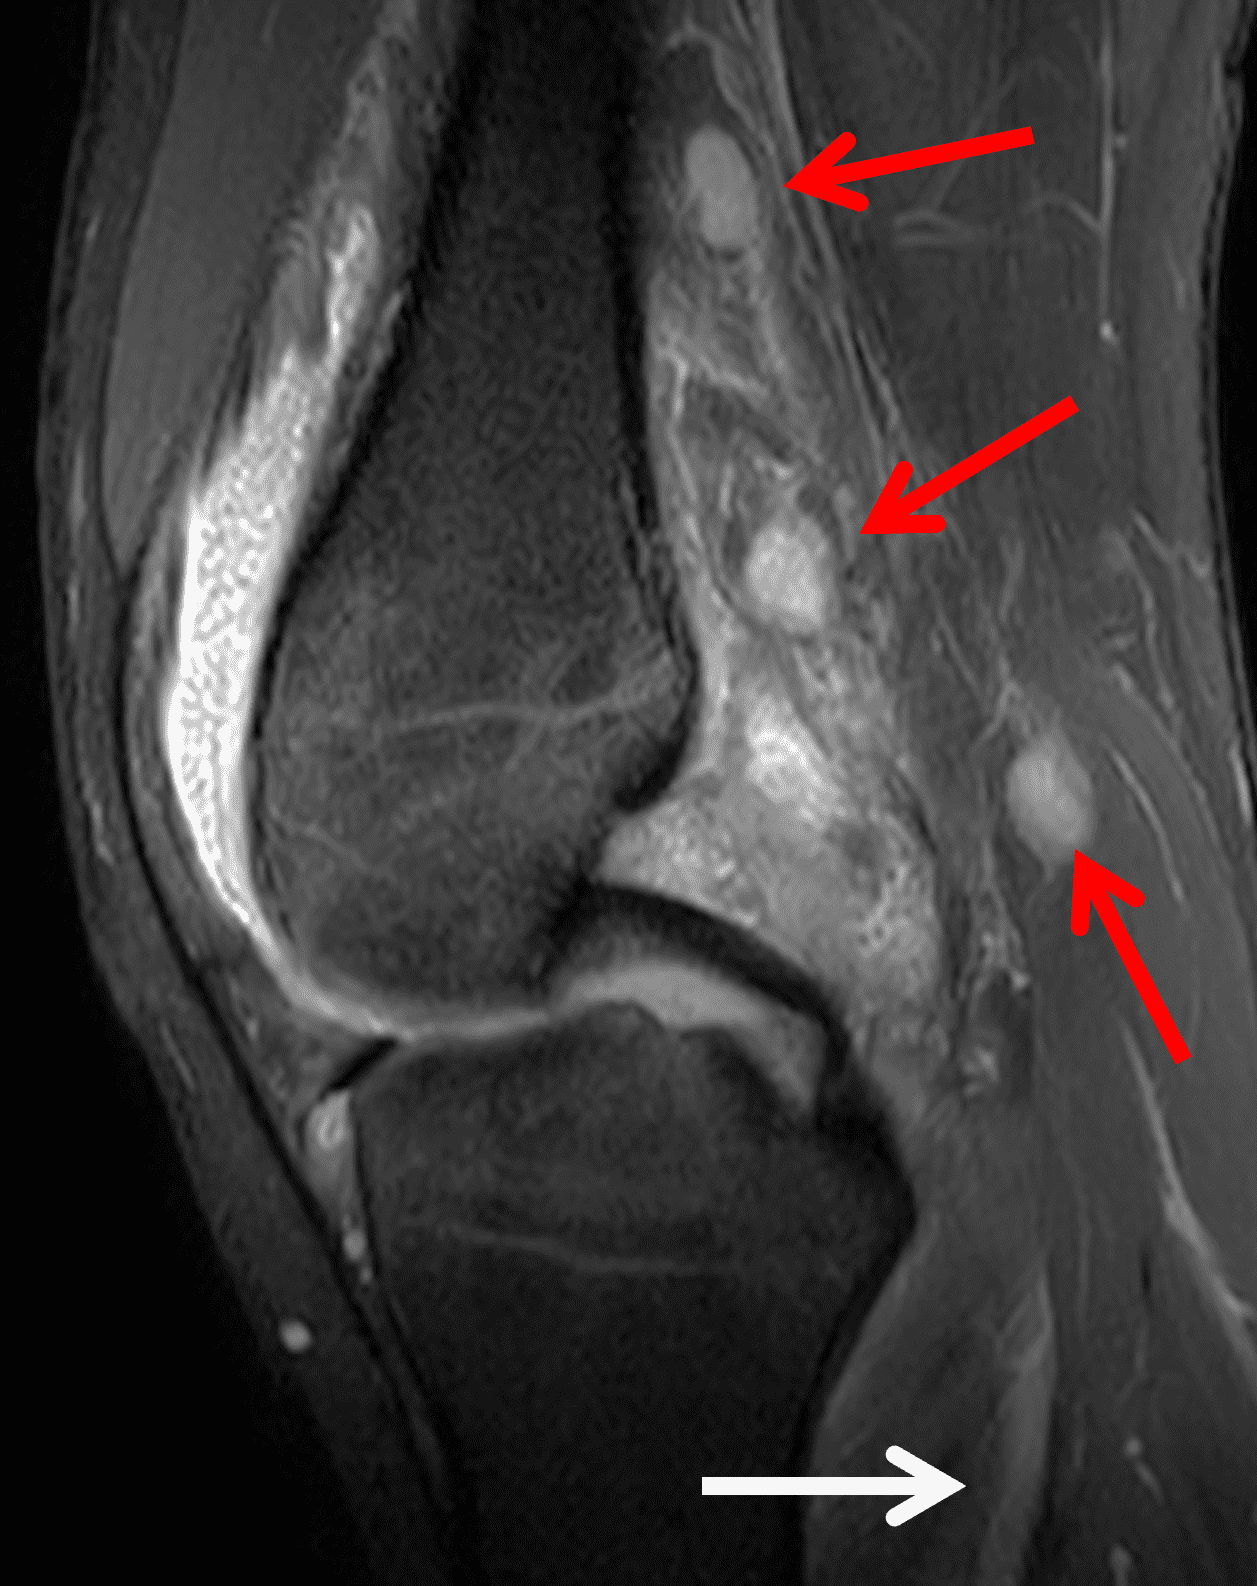

Figure 4: Lyme arthritis. Fat-suppressed, fluid-sensitive images. (4A) Transverse image shows severe proliferative synovitis in the anterior and posterior joint recesses (arrows). Note the lack of surrounding subcutaneous edema. (4B) In addition to synovitis, the sagittal image shows multiple reactive lymph nodes (red arrows) and popliteal myositis (white arrow). (4C) Coronal image also shows patchy non-joint centered marrow edema in the distal femur and proximal tibia (asterisks), which is uncommon in Lyme disease compared to acute septic arthritis.

Pediatric patients often present with a more acute clinical picture including fever, difficulty weight-bearing, elevated serum inflammatory markers, and elevated synovial white blood cell count, all of which can also be seen in the setting of acute septic arthritis due to other bacteria.5,9,12 Several studies have identified MR findings that help distinguish Lyme arthritis from septic arthritis for clinical decision-making. Both groups of patients will have synovitis and an effusion related to synovial inflammation and hyperemia. However, subcutaneous edema is highly associated with septic arthritis (Figure 5) and uncommon in Lyme arthritis. Marrow edema and erosions are much more common in septic arthritis, while osteomyelitis – actual infection of the bone – only occurs septic arthritis.2,3,9 Myositis can be seen in both conditions, but severe diffuse myositis is more highly correlated with septic arthritis (Figure 5).2